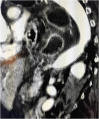

Introduction: The gastric volvulus is a rare condition in which the stomach, or part of it, rotates on its axis, for over 180°, constituting a surgical emergency. Even more rare is gastro-gastric intussusception. A delay in their diagnosis and treatment can have fatal consequences PRESENTATION OF CASE: An 82-year-old woman was admitted to the Surgery Unit with a two-day history of abdominal pain associated at first with coffee vomiting and, subsequently, with unproductive retching and oligoanuria. Physical examination showed severe dehydration, fever, at the abdominal level, palpation caused a marked tenderness of all quadrants, with signs of peritonism. Laboratory test showed showed neutrophilic hyperleukocytosis and high C reactive protein level. Abdominal computed tomography revealed an acute intrathoracic gastric volvulus and a gastrogastric intussuception. The patient was submitted to exploratory laparotomy, subtotal gastrectomy with Roux en Y anastomosis and simple plastic of the esophageal hiatus. At the end of the surgery, however, the patient died of your septic shock.

Discussion: The traditional treatment for a patient with acute gastric volvulus is an immediate surgical intervention to derotate the stomach and prevent vascular insufficiency. In the presence of necrosis or gastric perforation, resection should be performed. The few cases of gastrogastric intussusception described in the literature have been treated with sub-total gastrectomy and gastro-jejunal anastomosis. Any delay in diagnosis and treatment can prove fatal.